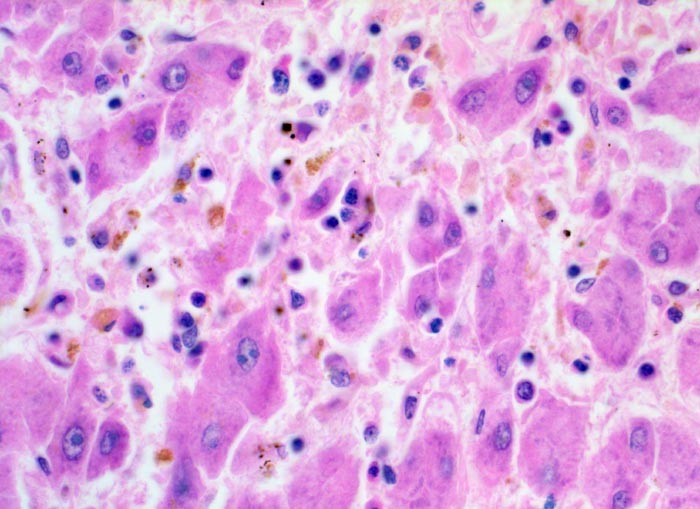

Das histologische Bild der akuten Hepatitis vom Virustyp ist gekennzeichnet durch eine lobuläre Entzündung bei fehlender portaler Fibrose und nur geringer entzündlicher Infiltration der Portalfelder. Es finden sich ballonierte Hepatozyten, Apoptosen (> 1164) und fleckige Nekrosen. Perivenuläre Nekrosen, Brückennekrosen oder konfluierende multilobuläre Nekrosen und eine läppchenzentrale Cholestase können vor allem in klinisch fulminant verlaufenden Fällen nachgewiesen werden. Zahlreiche Makrophagen, welche Diastase-PAS positives Zeroidpigment (> 4319) von phagozytierten nekrotischen Hepatozyten enthalten, zeugen im subakuten Stadium von einer abgelaufenen akuten Hepatitis mit Parenchymnekrosen. Eine Unterscheidung der verschiedenen Typen der viralen Hepatitis und einiger Formen medikamentöser Hepatitiden gelingt rein morphologisch aufgrund des unspezifischen Bildes meist nicht. Für eine ätiologische Klassifizierung sind zusätzliche klinische Angaben erforderlich (Anamnese, Medikamente, Serologie).

• Regelrechte Läppchenarchitektur.

• Lobuläre gemischte Entzündung.

• Ansammlungen zeroidbeladener Makrophagen innerhalb von Parenchymnekrosen (abgebaute fleckförmige Nekrose).

• Apoptosen (hypereosinophile abgerundete Leberzellen).

• Portale gemischte Entzündung.

• Fehlende Fibrose.